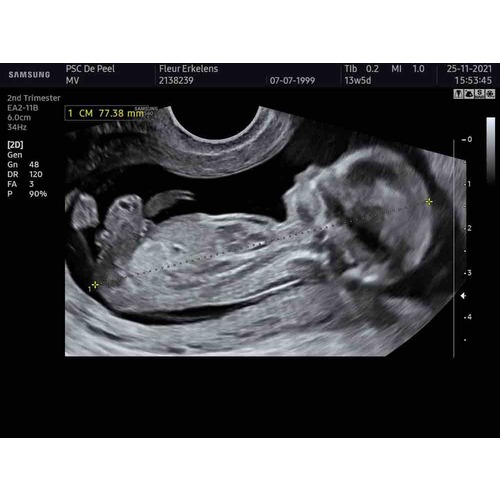

Is er iemand die hier iets uit kan halen qua geslacht?

Jongen

Jongen 馃槉